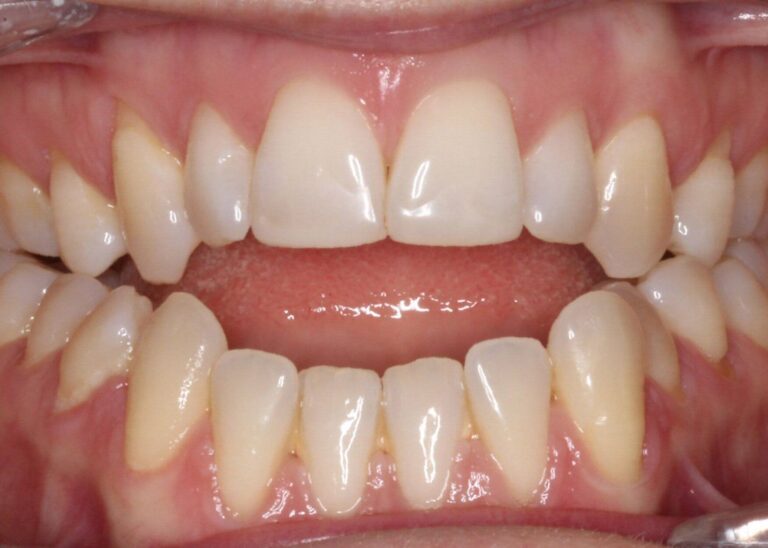

Дълбока захапка

Дълбоката захапка е най-често срещан проблем, при който горните предни зъби покриват вертикално долните зъби. В някои по-тежки случаи горните зъби могат да стигат до долните венци или долните зъби да опират в небцето. Дълбоката захапка най-често се проявява при вредни детски навици, ранна загуба на млечни зъби и несъответствия в растежа на челюстта.

Усложнения, които могат да настъпят – Ако не се лекува, дълбоката захапка причинява прекомерно износване на зъбите, повишена чувствителност, заболявания на венците и болка в челюстта.